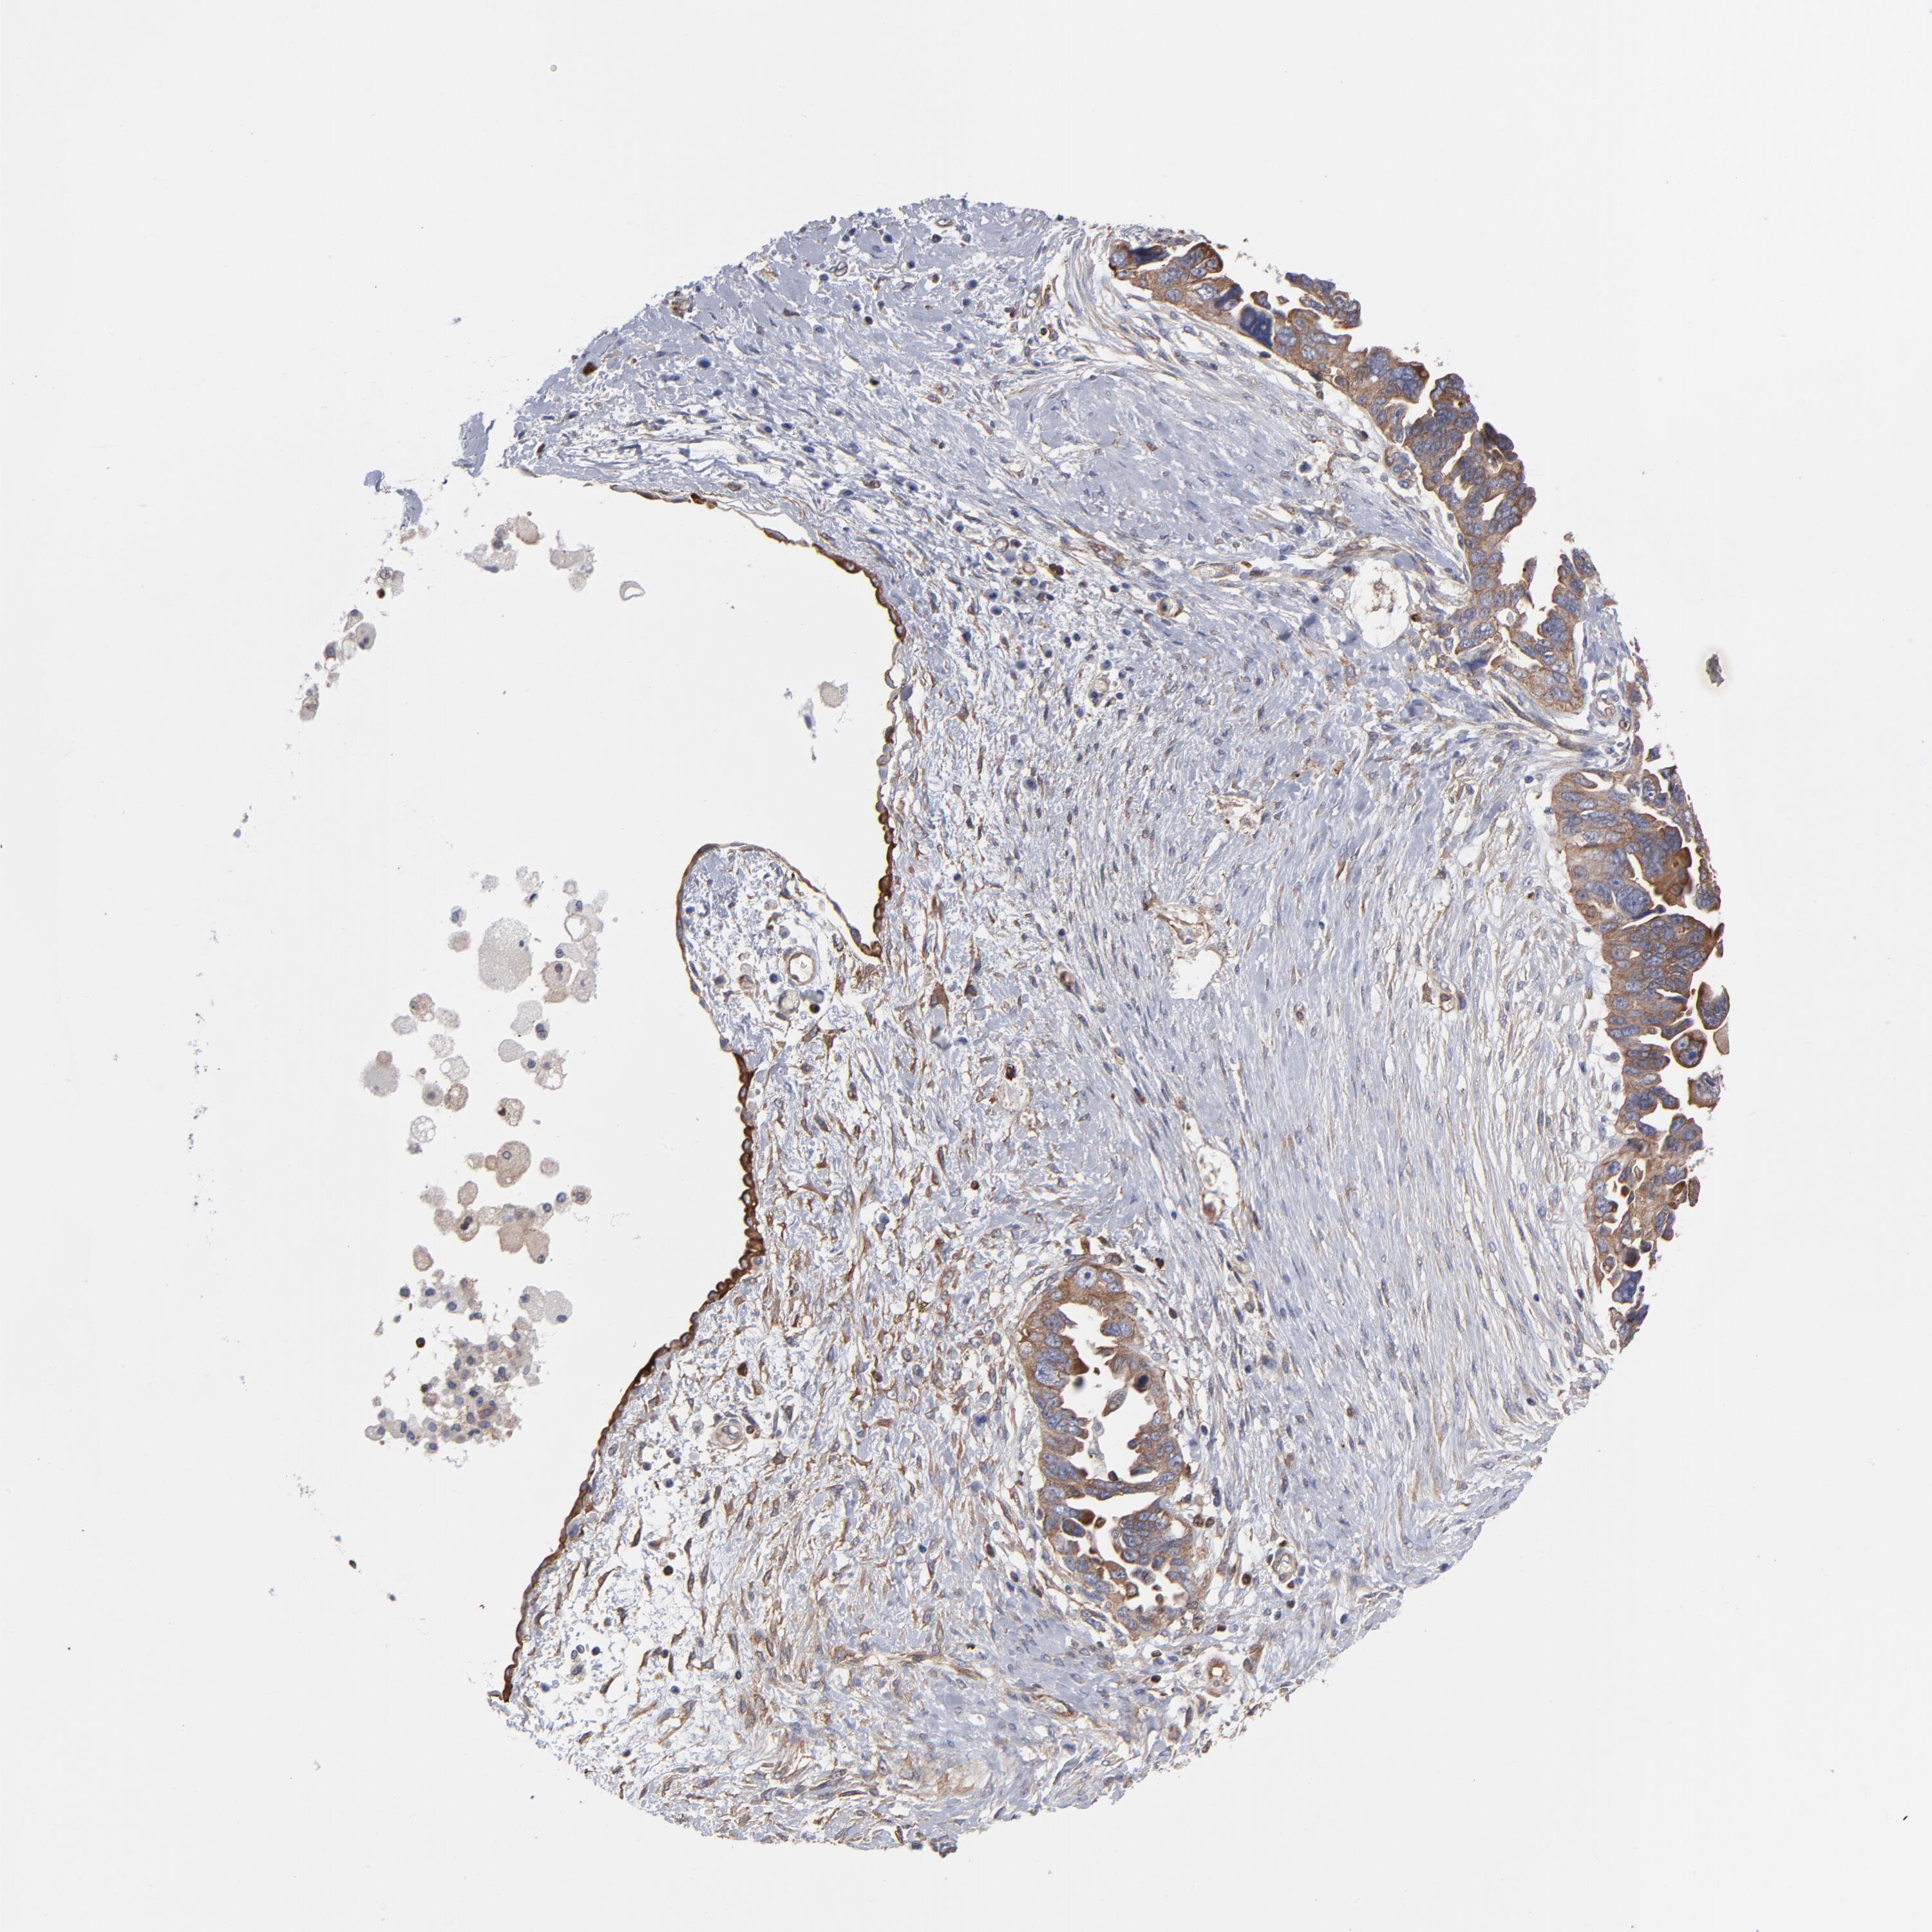

OVARIAN CANCER - Protein expressioni

A mouse-over function shows sample information and annotation data. Click on an image to view it in a full screen mode. Samples can be filtered based on level of antibody staining by selecting one or several of the following categories: high, medium, low and not detected. The assay and annotation is described here.

Note that samples used for immunohistochemistry by the Human Protein Atlas do not correspond to samples in the TCGA dataset.

Antibody stainingi

Antibody staining in the annotated cell types in the current human tissue is reported as not detected, low, medium, or high, based on conventional immunohistochemistry profiling in selected tissues. This score is based on the combination of the staining intensity and fraction of stained cells.

Each image is clickable and will lead to virtual microscopy that enables deeper exploration of all samples and also displays staining intensity scores, fraction scores and subcellular localization as well as patient and tissue information for each sample.

Antibody CAB003841

Staining

High

Medium

Low

Not detected

Intensity

Strong

Moderate

Weak

Negative

Quantity

>75%

75%-25%

<25%

None

Location

Nuclear

Cytoplasmic/membranous

Cytoplasmic/membranous,nuclear

Cystadenocarcinoma, mucinous, NOS

Carcinoma, endometroid

Cystadenocarcinoma, serous, NOS